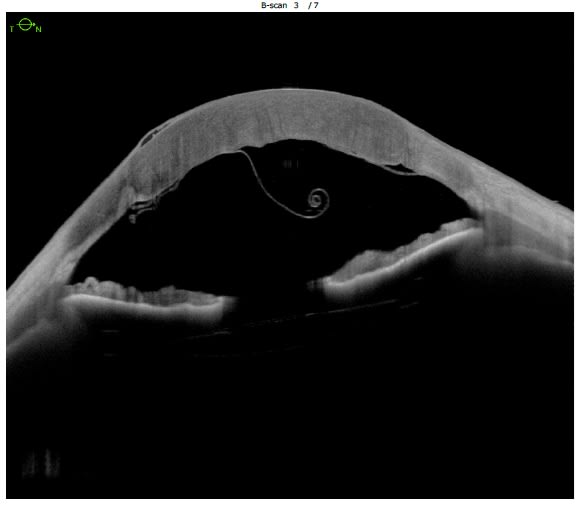

A well-fitting scleral contact lens will clear the cornea and limbus by precise amounts, and land evenly on the sclera. Anterior-segment (AS)-OCT gives precise views of central and limbal clearance. Aligning a scleral lens chamber to the peri-limbal area can be a challenging part of a fitting, especially in eyes that are significantly irregular in shape due to their post-surgical status. An example: Those that have undergone radial keratotomy or corneal transplantation. An AS-OCT can assist in modifications that are difficult to assess in the slit lamp.